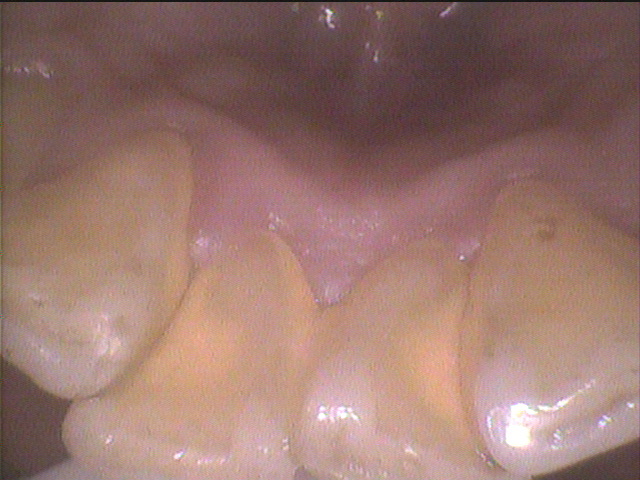

◎クリーニング前のお写真

初診で来院された患者さんで、久しぶりのクリーニングだったそうです。

歯ブラシでは取り除けない固い歯石がたまっていたので超音波の機械を使って除去しました。